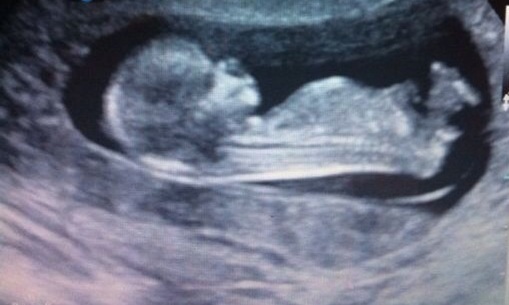

Is there something vissible at one of these scans? It was taken at 13+4 weeks. I will really appriciate your guess! Can you also say why you are thinking boy or girl?

Thinking boy - the nub is pointing upward in relation to the spine. Congrats!

I say boy based off second pic...nub is angled up.

50/50 so far.. Is it possible for a boy to have a forked nub?